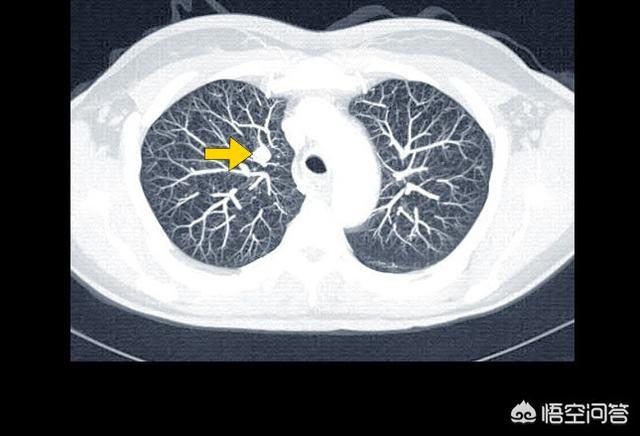

Dieser Patient war erst 39 Jahre alt, litt unter Engegefühl in der Brust und Kurzatmigkeit und wurde mit einem Adenokarzinom der rechten Lungenseite diagnostiziert, mit einem großen Pleuraerguss und Funktionsverlust der gesamten rechten Lunge. Ein so schwerwiegender Zustand ist bei älteren Menschen etwas häufiger, und wenn er nicht behandelt wird, kommt es bald zum Atemstillstand. Glücklicherweise spricht sie gut auf eine gezielte Therapie an und lebt nun seit mehr als drei Jahren mit dem Tumor, wobei ihr Pleuraerguss unter Kontrolle ist.